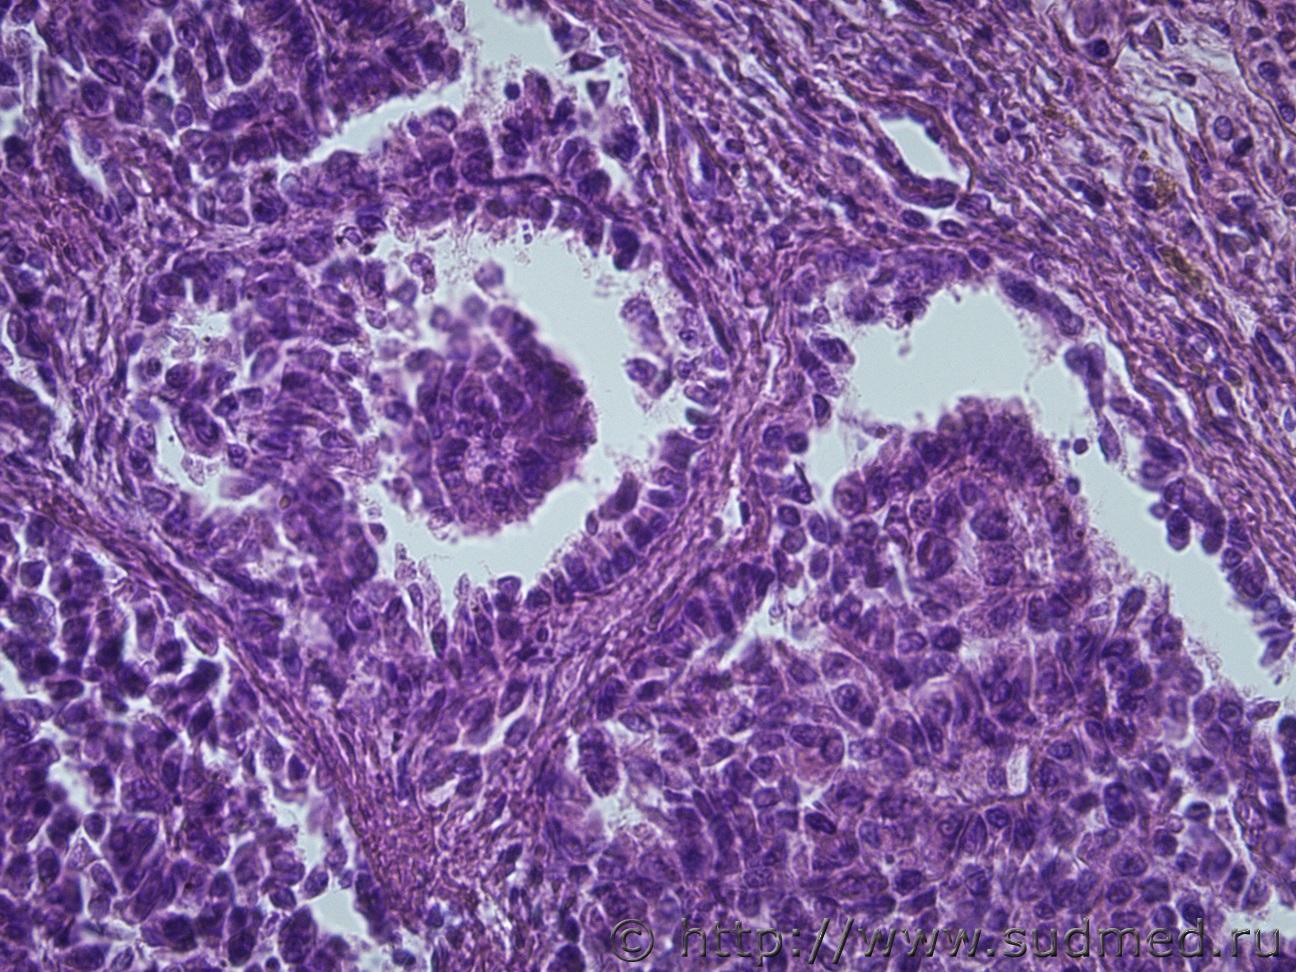

Жен 62 года. На задней поверхности левой почки желтовато-сероватый участок 1на1 см, творожистой консистенции.Судебная медицина - Прикрепленное изображение Судебная медицина - Прикрепленное изображениеСудебная медицина - Прикрепленное изображениеСудебная медицина - Прикрепленное изображениеСудебная медицина - Прикрепленное изображение

Почечноклеточный рак,другого не придумал. wink.gif

Меня тоже посещает мысль, что это почечно-клеточный рак, папиллярный тип)))